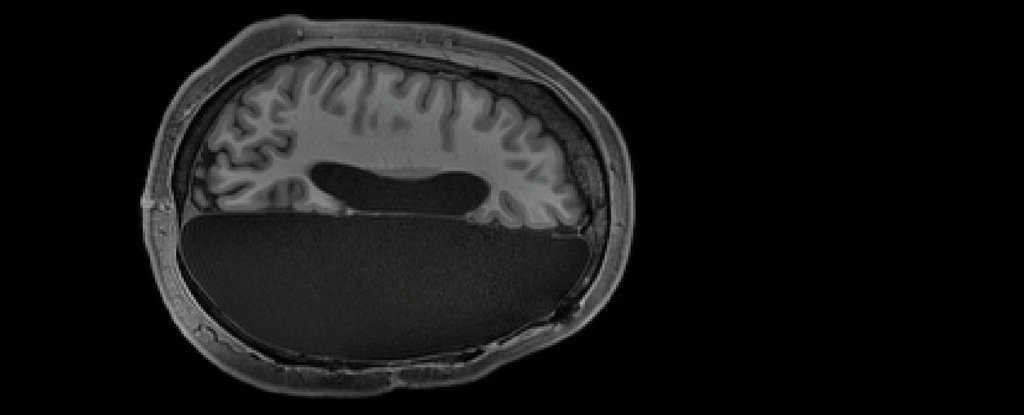

ScienceTechyNews: Remarkable MRI Study Reveals How Some People Function With Only Half a Brain

No hemisphere? No problem.